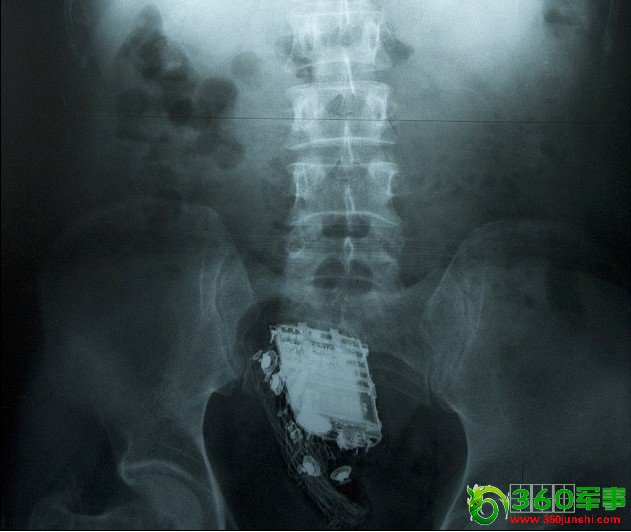

斯里兰卡一名囚犯为了躲避检查,竟然将手机藏进屁股里。